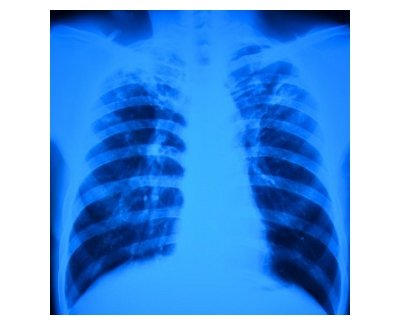

Esta Jornada para profesionales de la salud se desarrollará bajo el título de «Tuberculosis en España: realidad y compromiso», situará en primer plano este problema de salud pública, mediante las ponencias de expertos en este ámbito y el posterior debate con los profesionales presentes.